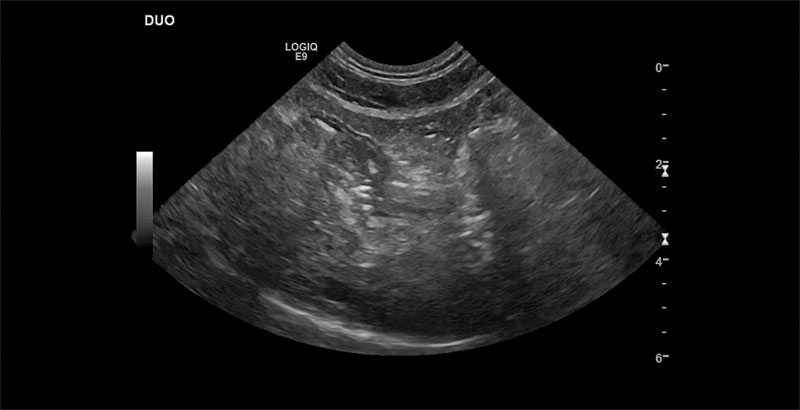

An eight-year-old F/S domestic shorthair underwent aFAST and was identified to have free gas.

2) Figure 2. An eight-year-old F/S domestic shorthair presented for vague GI signs of 48 hours, with a decreasing appetite, and then abruptly stopped eating with only one episode of vomiting. I was unsure if what I saw on my initial FAST scan (free gas in the belly) was an artifact or real until the radiographs suggested free gas near the diaphragm on the ventral dorsal view. The radiologist performed a full ultrasound and confirmed the presence of free gas in the abdomen. Despite no fever, she had a perforated intestine with no apparent mass identified.

Figure 2 shows that while we can be diagnostic in many cases, we always need to consider/recommend evaluation by a specialist (radiologist, internist, or criticalist especially trained for complete ultrasounds) as there are limitations to what aFAST scans can identify and will vary depending on the individual’s training and equipment available.